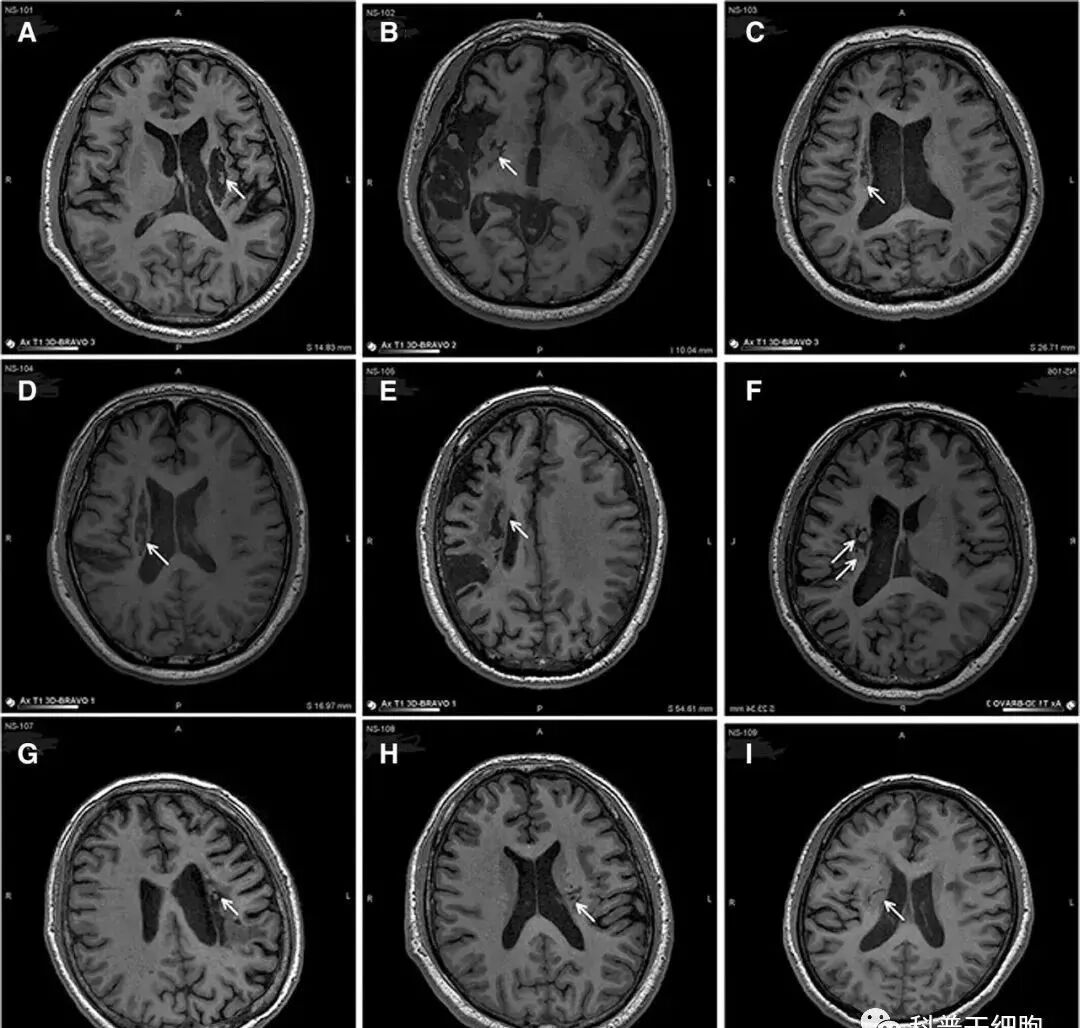

图片

△ 9名患者的影像学显示病变区域的组织都发生了明显变化

影像学研究的结果表明,干细胞植入区出现了新的神经组织,这也证明了人源神经干细胞治疗偏瘫性脑卒中拥有一定的临床益处。